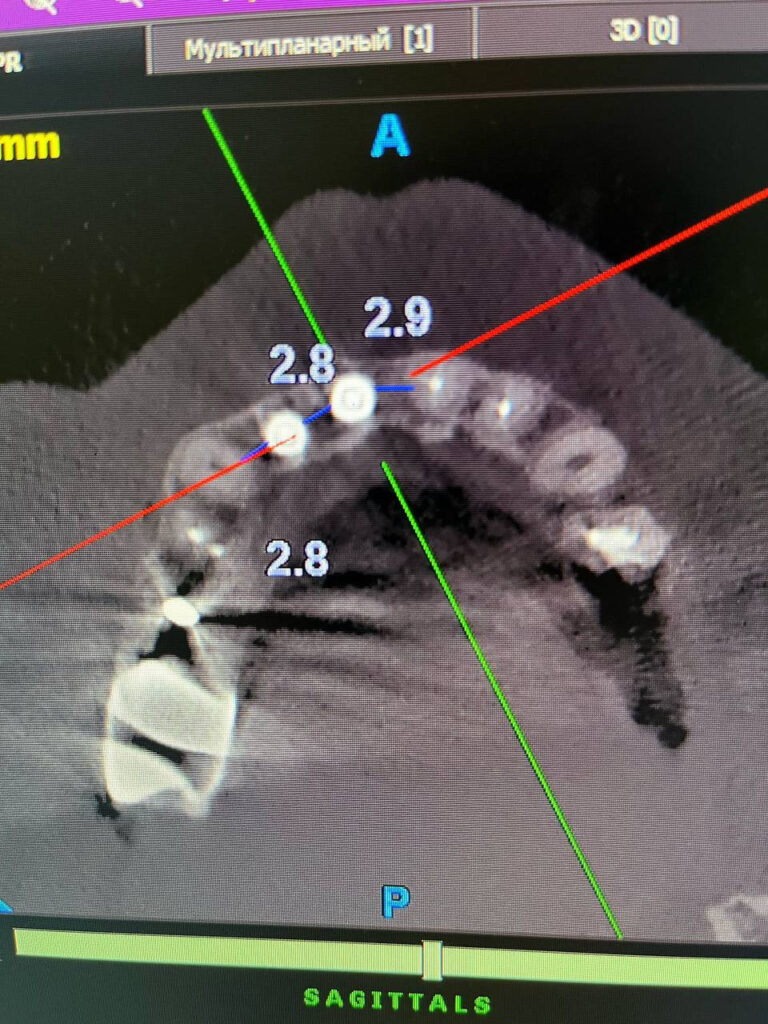

Конусно-лучевая компьютерная томография (КЛКТ) позволяет:

- Видеть кости, нервы, корни и синусы в 3D

- Точно планировать имплантацию

- Находить скрытые проблемы (кисты, воспаления и др.)